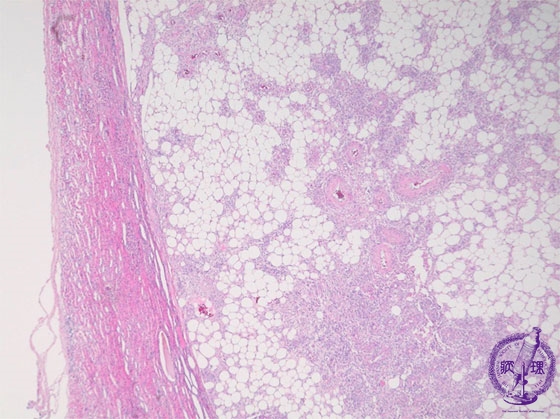

- (18)Angiomyolipoma(Tuberous sclerosis)

Microscopic findings ( HE, low power view): The tumor is clearly bordered (yellow dotted line) with adjacent compressed renal parenchyma.